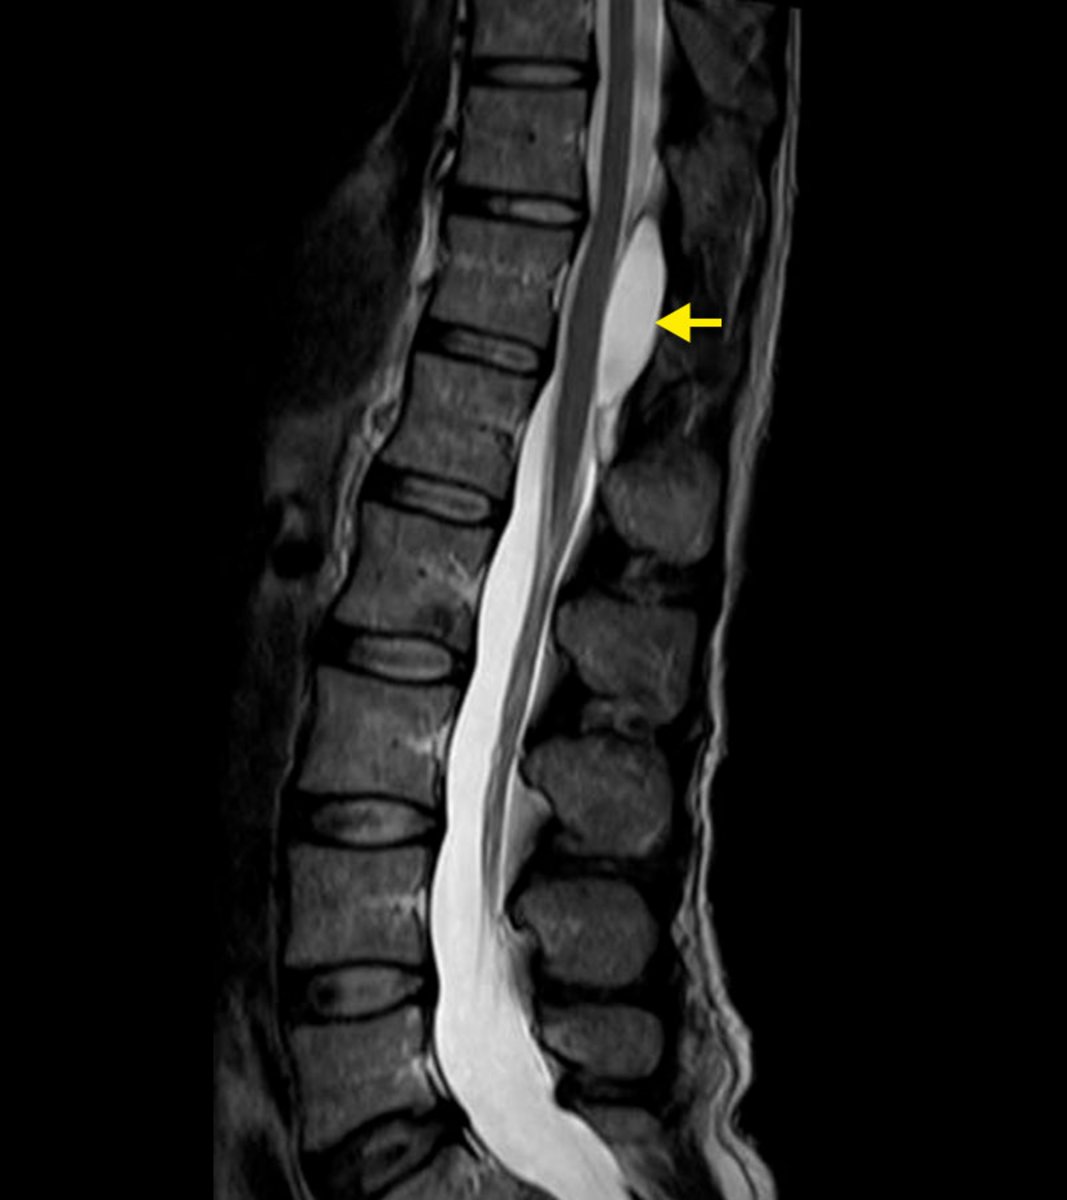

spinal ependymoma

central cord (arise from central canal)

enhancing

often cystic looking

often associated syrinx